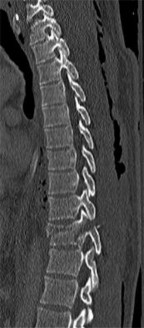

A 16-year-old male is brought to the clinic by his mother, who is concerned about his "round back." He complains of dull mid-back pain after standing for long periods. Standing lateral radiographs reveal a thoracic kyphosis of 65 degrees.

According to the Sorensen criteria, what specific radiographic finding is required to confirm the diagnosis of classic Scheuermann's disease?